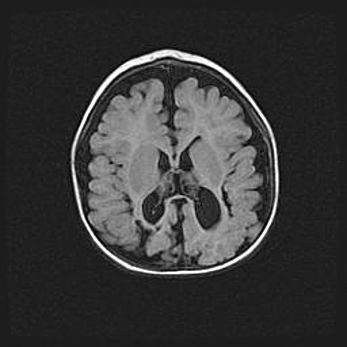

Открытая гидроцефалия.

Возраст: 6 месяцев 15 дней

Вес: 6200 г

Пол: женский

Окружность головы: 41 см

Срок гестации: 38 недель

Гидроцефалия головного мозга у новорожденных – это скопление избыточного количества цереброспинальной жидкости в головном мозге. Ее избыточное скопление в мозге приводит к патологическому расширению желудочков мозга (четырех полостей, расположенных в глубине белого вещества мозга, заполненных цереброспинальной жидкостью и связанных узкими проходами).

Открытый тип гидроцефалии (сообщающаяся) наблюдается тогда, когда нарушен механизм всасывания ликвора в системный кровоток. При этом типе причиной заболевания чаще всего является перенесенные ранее инфекции (например: менингит),  либо же наличие крови в субарахноидальном пространстве.